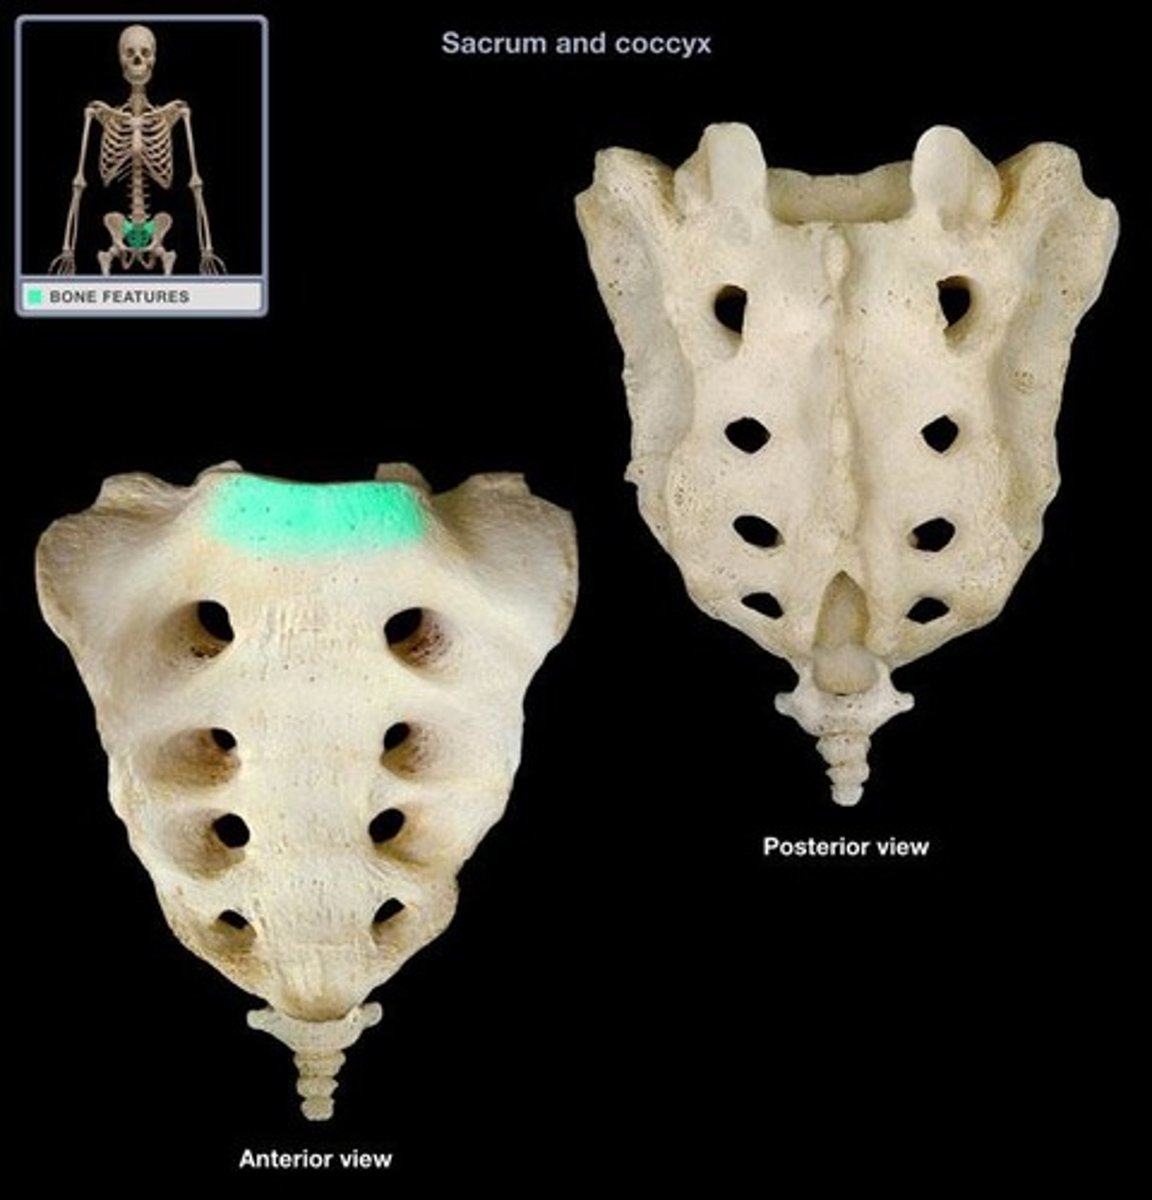

S1-S5

how many sacral vertebra are fused together

1-3

how many coccyx vertebra are fused together

what does the sacral promonatory line tell u

promonatory

S1

what level is the promonatory located

sacral canal

nerves coming from cauda equina, extension of vertebral formamen

what runs thru the sacral canal

true

t/f: rectum follows curve of the sacrum

true

t/f: there are lymph nodes that follow the curve of the sacrum

S1 down

what are the vertebral ranges for the pelvic region